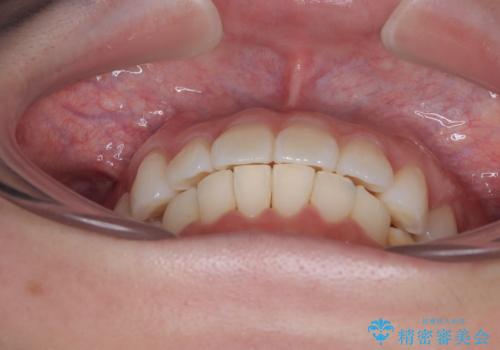

- 上下前歯の叢生を気にして来院された患者様です。

軽度な叢生であり、安価で短期間の治療を規模されていたため、インビザライン・モデレートを用いて矯正治療を行うこととしました。